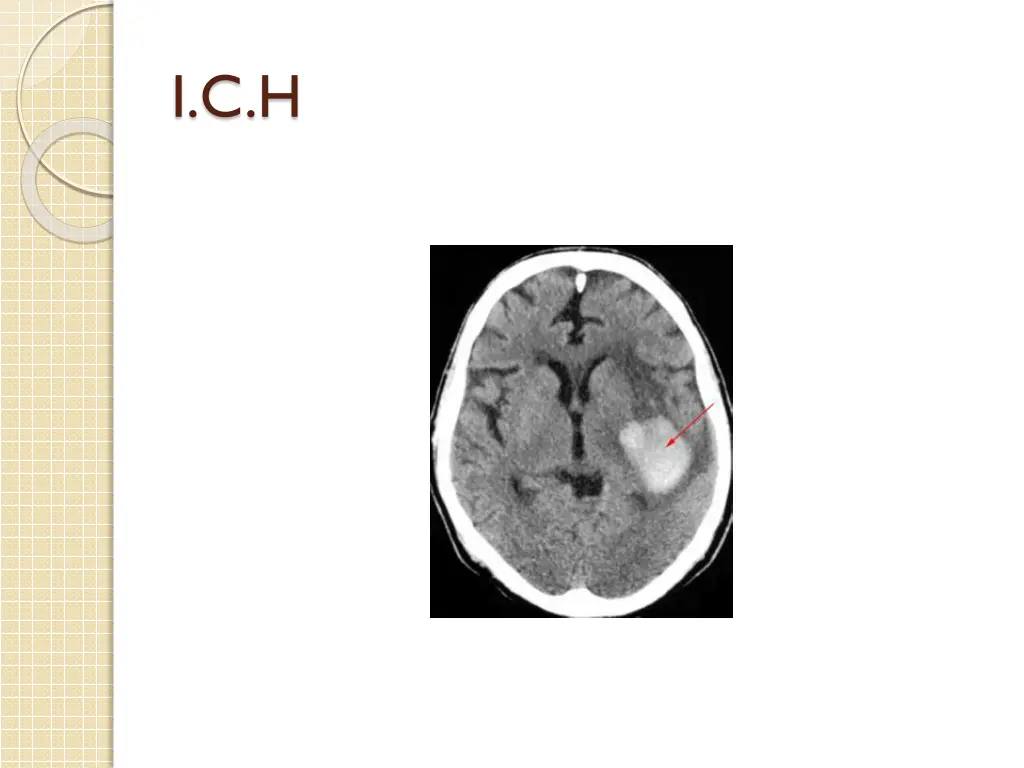

2- focal inj.:defined as visible damage that is generally limited to a well circumscribed region; e.g contusions(coup &countercoup),SDH,EDH,S.A.H,ICH,IVH Occur in half of all pat. With severe brain inj., ,and 2/3 of brain inj.related death.